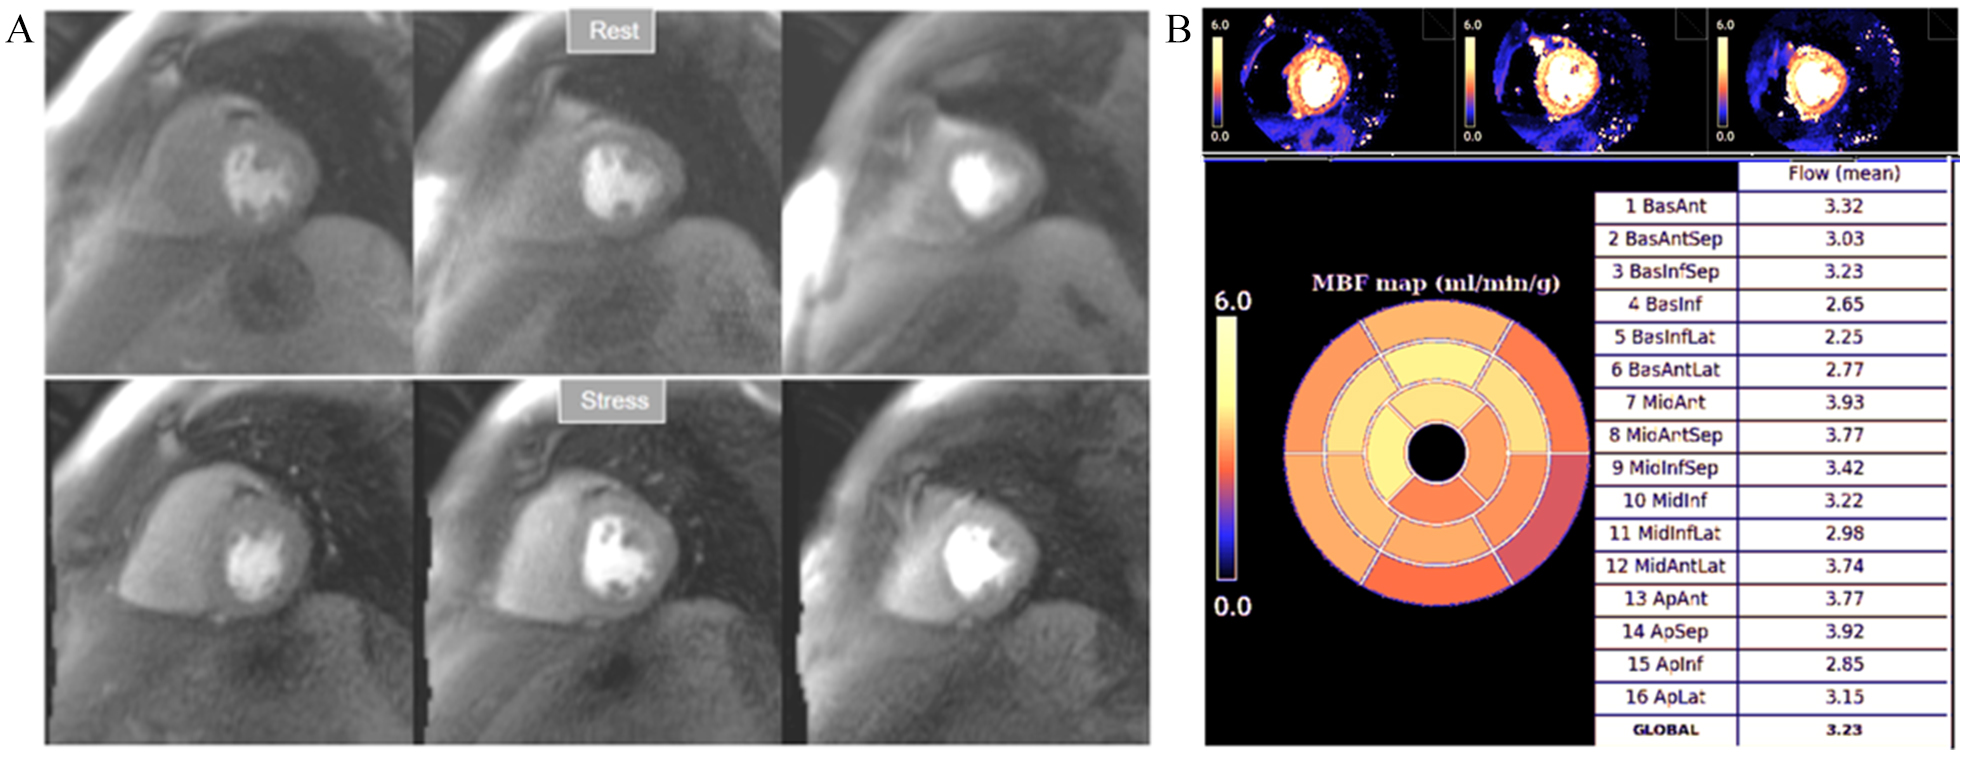

More recently, a new method has been proposed [56] that includes several important solutions contributing to a reliable implementation on the routine workflow of a CMR exam [57]. Firstly, it is based on a dual imaging sequence strategy (Fig. 24), where low-resolution blood pool images used for estimation of the AIF are followed by multi-slice 2D high-resolution myocardial perfusion sequence. The total duration of the scheme is around 500 msec, that allows for the obtention of 3 slices sampled every heart cycle, as long as the heart rate is below 120 b.p.m. AIF extraction from the low-resolution sequence has proven to be reliably obtained automatically [58] (Fig. 25). Second, motion and surface coil intensity correction are applied to both AIF and perfusion images [57, 59]. Third, a process of SI conversion into gadolinium concentration [Gd] units is performed for both sequences [56] (Fig. 26). Fourth, and most important, AIF [Gd] curve and perfusion [Gd] images are inputted into flow mapping step for pixel-wise myocardial flow mapping [57] rendering quantitative values of MBF (in mL/min/g) (Fig. 27). Based on a process of deep learning [60], myocardial segmentation and allocation of flow values are automatically processed (Fig. 28) and integrated into the MRI scanner using the Gadgetron streaming reconstruction software [61, 62]. The final output of the process consists on a bull’s-eye plot of color-encoded MBF values on the LV 16-segment model, and the listed numerical values of absolute flow at stress and at rest and, also, the derived MPR, each of them calculated for the endo- and epicardial halves of the segment (Fig. 29). The presence of inducible perfusion defects is thus detected not only visually on the perfusion color map, but also quantitatively estimated by the absolute values of stress MBF and the corresponding MPR of the involved myocardial segments (Fig. 30). Of note, in case of a suboptimal effect of the vasodilator agent, a lack of increase in stress MFB and MPR values is observed, leading to a potentially false positive diagnosis, in contrast with the visual assessment of perfusion, which, in this case, as stated above, would not show induced defects, with the potential for a false negative.

Fig. 32.Normal perfusion mapping. (A) Rest and stress perfusion studies showing absence of induced visual defect. (B) Normal global and segmental stress MBF.